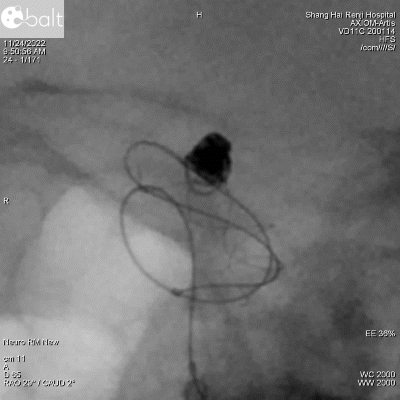

图5:微导丝(Synchro 14)成襻通过支架内腔,可以看到支架近端轻微向前移动。

图6:微导管(Echelon 10)跟上,给予适当张力,微导管呈弧形、支架内按摩,确保支架在大弯侧充分贴壁。

图8. a:微导丝微导管按摩前。b:微导丝微导管按摩后。可以看出按摩操作有效促进了支架近端贴壁,同时支架近端进一步向前短缩。